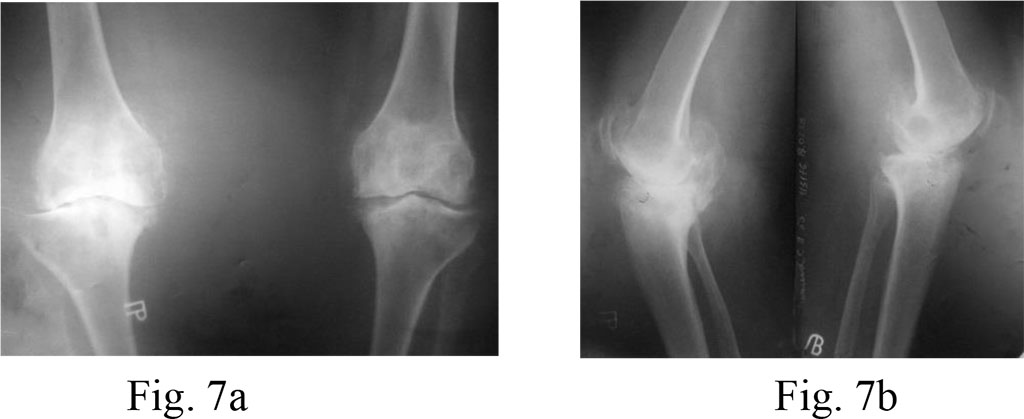

Diagnosis: bilateral deforming gonarthrosis stage 4; varus deformities of both knees.

Surgical treatment: bilateral total knee arthroplasty with PCL preservation.

On the right, we carried out tibial resection on the level of the lower edge of the defect and applied a large tibial insert (21 mm). On the left, resection of the tibial bone was on the level of the upper edge of the lesion, than filled with bone cement and a tibial insert of a minimal size (9 mm) (Fig. 7a, b and 8a, b)